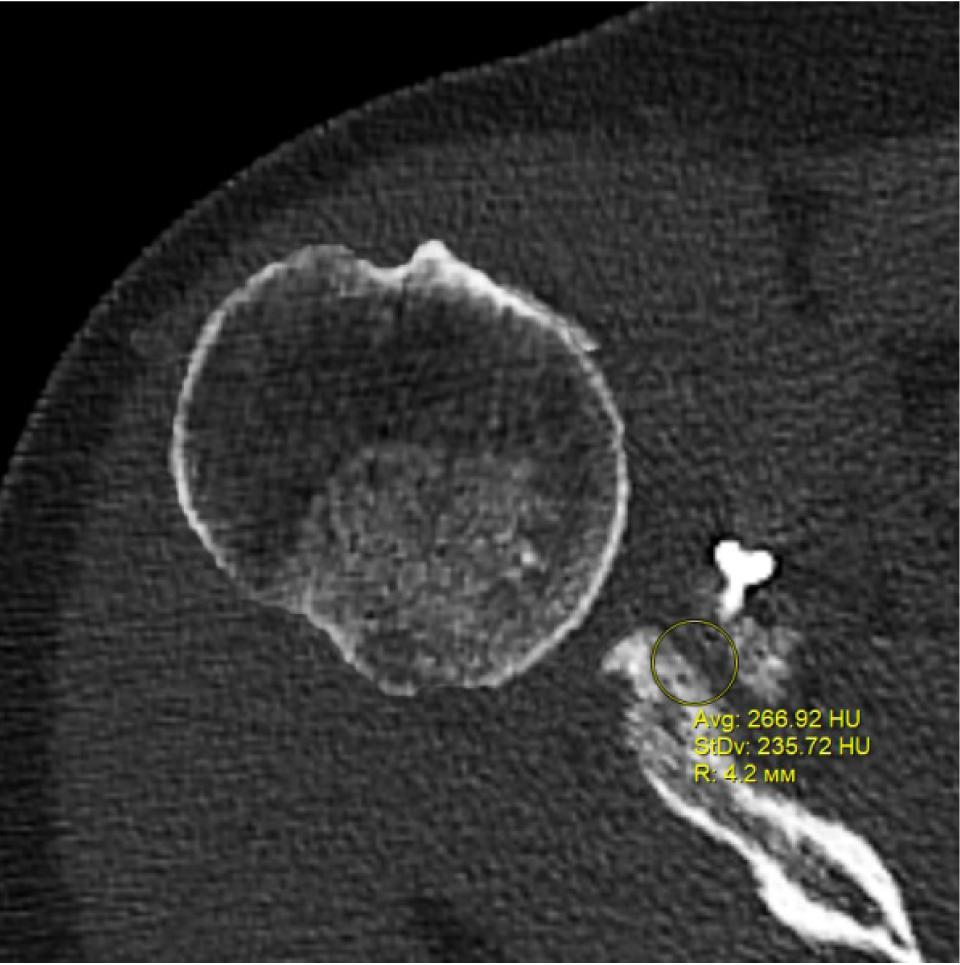

В программном обеспечении, на аксиальных КТ срезах оперированного плечевого сустава, выбирали инструмент «круг», который позволял посчитать среднюю плотность тканей внутри круга в единицах Хаунсфильда. Шкала единиц Хаунс-филда (HU) – шкалалинейного ослабления излучения по отношению к дистиллированной воде, рентгеновская плотность которой была принята за 0 HU (при стандартных давлении и температуре). Круг устанавливали таким образом, чтобы одна его половина была заполнена тканью гленоида, вторая половина тканью трансплантата (рис. 1–3). Оценивали плотность тканей над проксимальным винтом, между винтами, под дистальным винтом. Полученные данные анализировали с помощью пакета Microsoft Excel.

Рис. 2. Оценка плотности ткани между винтами

Через 3 месяца после оперативного лечения по данным анализа КТ срезов были получены следующие результаты: плотность ткани над проксимальным винтом составили (424 ± 24,3) HU, между винтами (460 ± 23,4) HU, под дистальным винтом (587 ± 49,1) HU. Спустя 6 месяцев после операции плотность ткани над проксимальным винтом составили (320 ± 28,7) HU, между винтами (424 ± 36,2) HU, под дистальным винтом (623 ± 33,4) HU. Через 12 месяцев после операции показатели были следующие над проксимальным винтом (276 ± 22,1) HU, между винтами (387 ± 31,1) HU, под дистальным винтом (662 ± 43,2) HU (таблица).